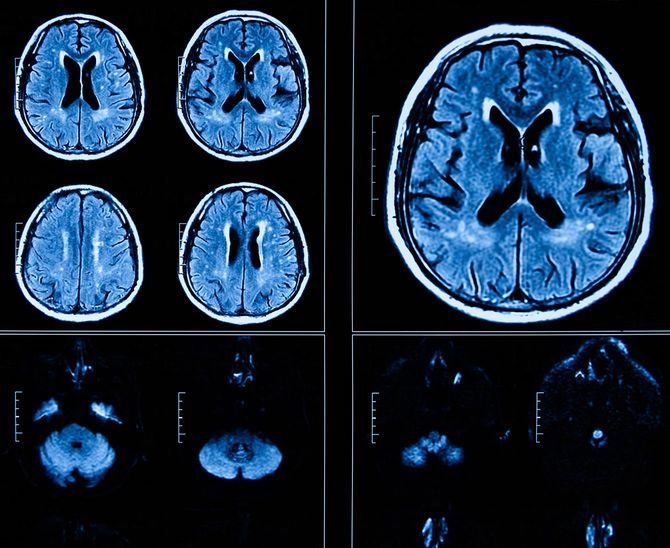

脳の老化は、こうした記憶障害よりはるかに前に前頭葉で起こっている。実際、CTやMRIのような頭の写真をみても40代から頭蓋骨と脳の前頭葉にあたる部分に隙間が見えるようになる、つまり委縮が目で見えるようになるのだ。